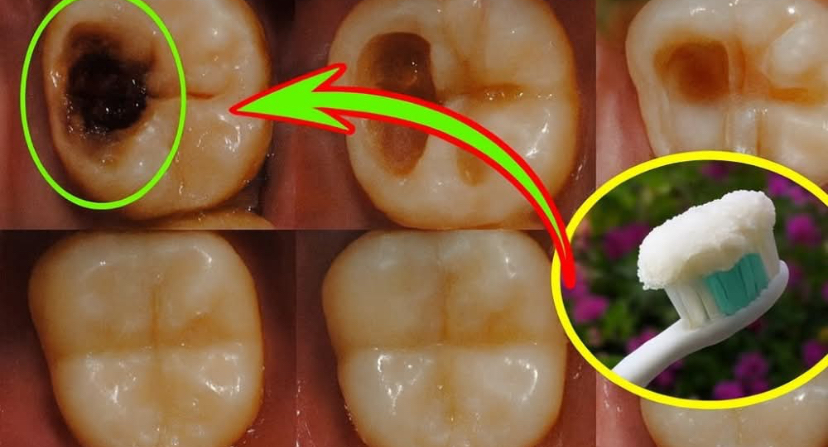

Cavities form when harmful bacteria in your mouth produce acids that erode your tooth enamel, the protective outer layer of your teeth. Left unchecked, these tiny holes can deepen, leading to pain and costly treatments. But here’s the exciting truth: your teeth are living structures capable of remineralization, a process where enamel rebuilds itself with minerals like calcium and phosphate. By combining the antimicrobial power of ginger with the right toothpaste and a few smart habits, you can halt early decay in its tracks and fortify your teeth. Let’s explore how this dynamic duo—ginger and toothpaste—leads the charge in your fight for a healthier smile.Your diet is the foundation of a cavity-resistant smile. To supercharge the effects of your ginger-toothpaste blend, focus on foods that strengthen enamel. Calcium-rich choices like cheese, yogurt, and almonds provide the building blocks for robust teeth. Vitamin D from fatty fish, egg yolks, or sunlight exposure enhances calcium absorption. Magnesium in spinach, nuts, and seeds supports enamel structure, while phosphorus in eggs, fish, and lentils works with calcium to rebuild your teeth.Avoid sugary snacks, acidic sodas, and processed carbs, which feed cavity-causing bacteria. By prioritizing whole, nutrient-dense foods, you’re starving harmful bacteria and giving your enamel the tools to repair itself. Every bite is a step toward a stronger smile.Ready to harness this natural remedy? Crafting a ginger-toothpaste blend is simple, affordable, and incredibly effective. Here’s how to do it:Grate Fresh Ginger: Start with a small piece of fresh ginger (about 1 inch). Peel and finely grate it to release its potent juices.Mix with Toothpaste: Combine 1/2 teaspoon of grated ginger with a pea-sized amount of your chosen remineralizing toothpaste. Stir until well-blended.Brush Gently: Apply the mixture to your toothbrush and brush for two minutes, focusing on areas with early decay. Rinse thoroughly afterward.Use Sparingly: Apply this blend 2-3 times a week to avoid gum irritation, as ginger can be potent. On other days, stick to your regular toothpaste.This simple ritual delivers ginger’s antibacterial benefits directly to your teeth, while the toothpaste’s minerals support enamel repair. It’s a natural, powerful way to fight cavities at home.

A tiny cavity can spark a wave of dread